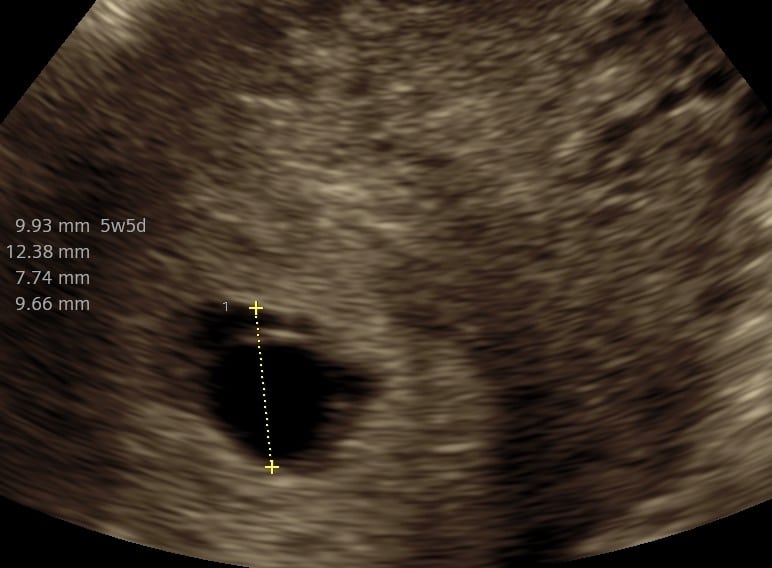

Praksisjordemoders tidlige tryghedsscanning (uger 5+0‑7+0) giver dig muligheden for:

- at bekræfte graviditet i livmoderen,

- at se hjerteblink, fra 6+3

- at få en foreløbig terminsberegning og stille spørgsmål til jordemoderen.